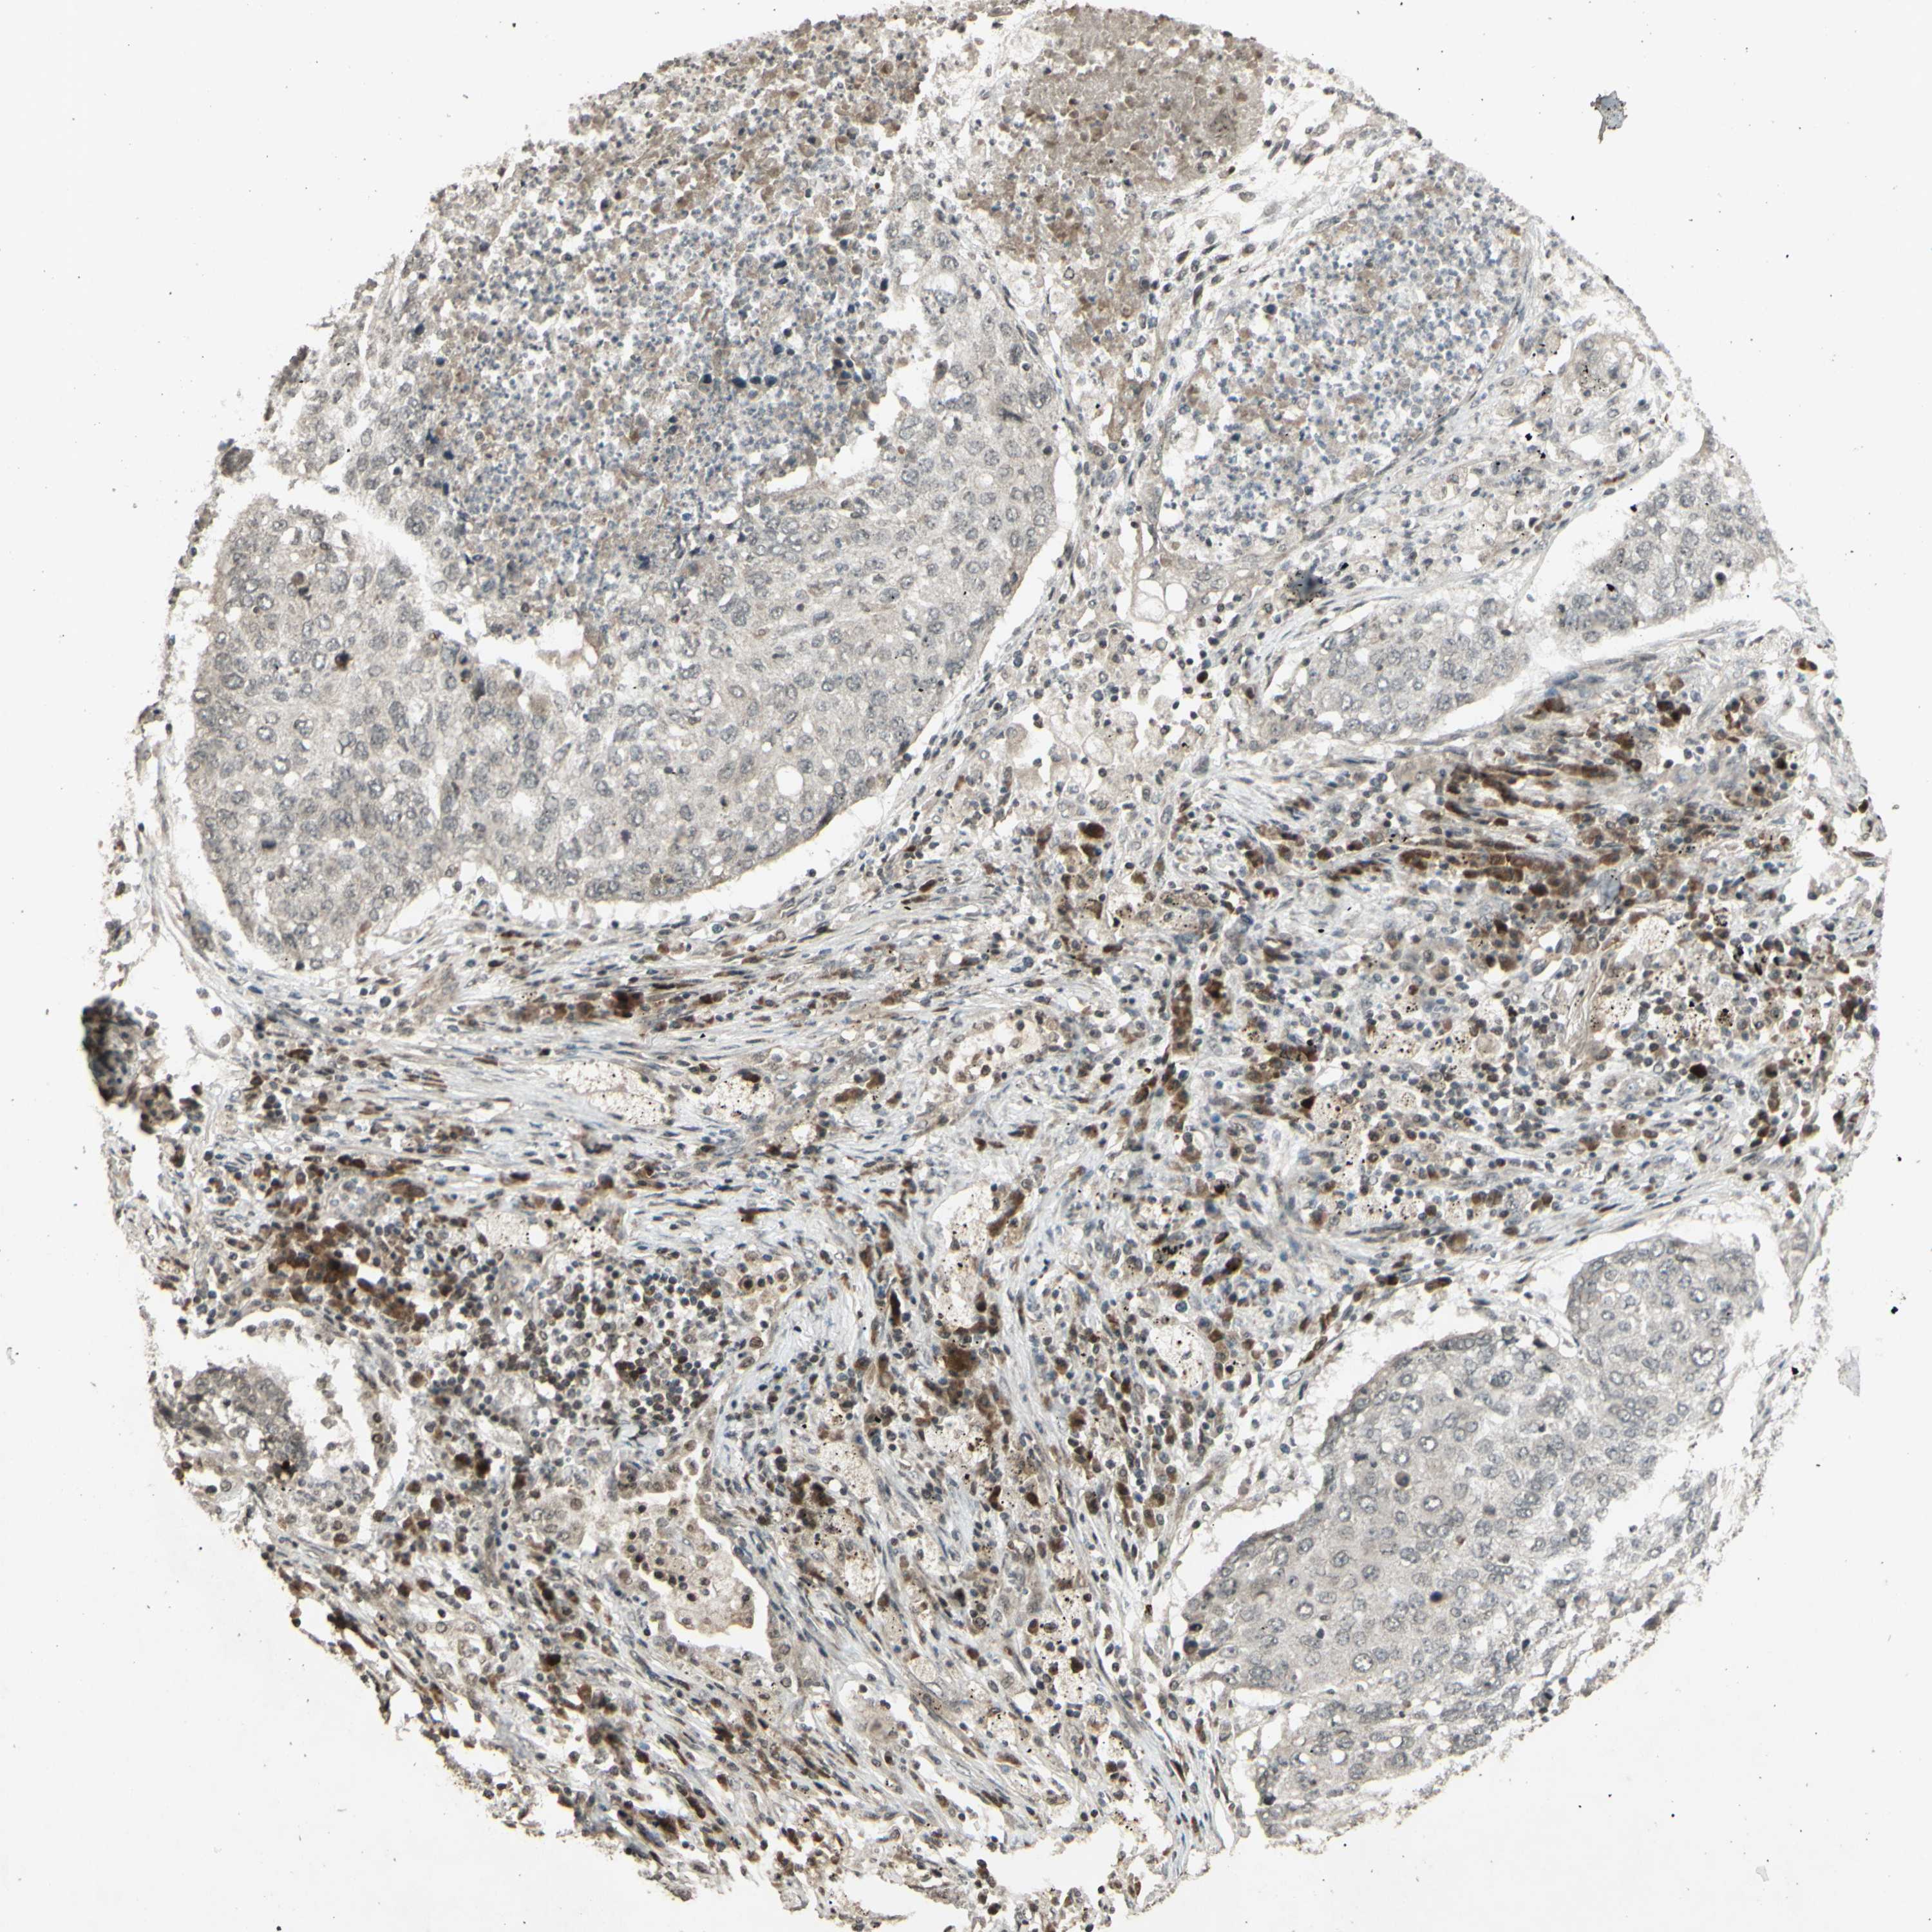

CANCER LUNG CANCER Show tissue menu

LUAD TCGA LUAD VALIDATION LUSC TCGA LUSC VALIDATION PROTEIN LUAD CPTAC PROTEIN LUSC CPTAC PROTEIN EXPRESSION